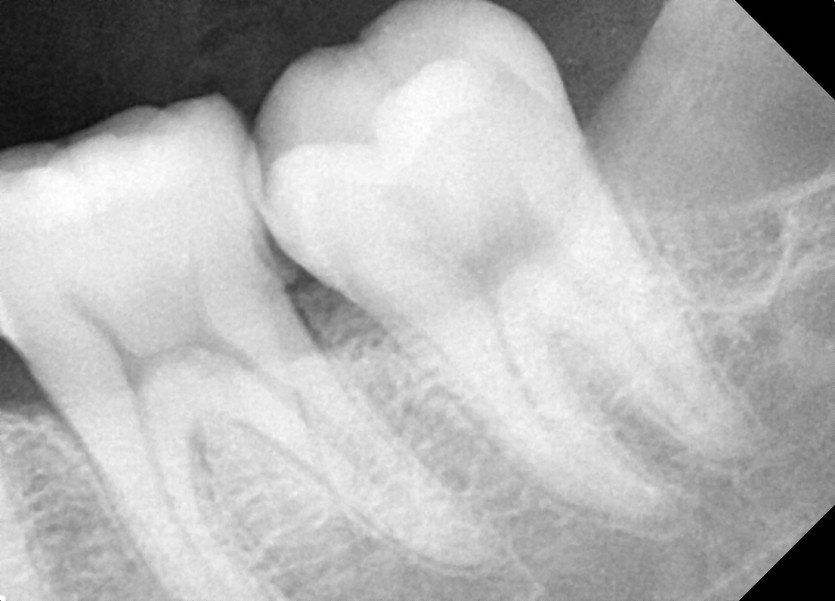

#38 사랑니 발치

구강 외과 전문의가 당일 발치했습니다.